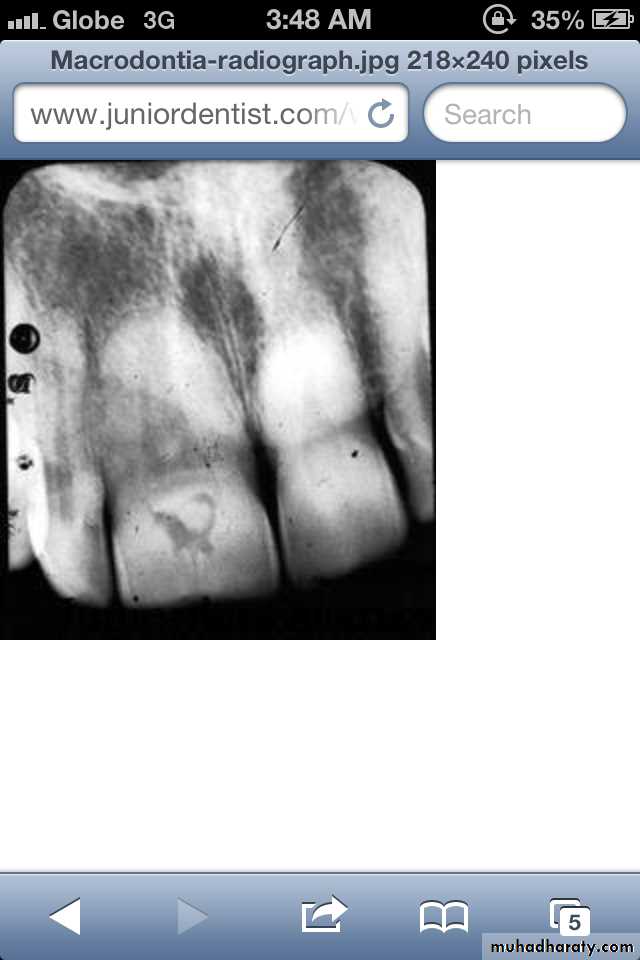

Macrodontia: the teeth are larger than normal, or the teeth are of normal size but occur in smaller than normal jaws.

(1) True Generalized Macrodontia

(2) Relative Generalized Macrodontia

(3) Focal or Localized Macrodontia

all teeth are larger than normal.

associated with pituitary giantism.exceedingly rare.

(1) True Generalized Macrodontia:

Normal or slightly larger than normal teeth in small jaws results in:

crowding of teethmalocclusion

impaction may occur.

(3) Focal/Localized Macrodontiauncommon condition.

unknown etiology.